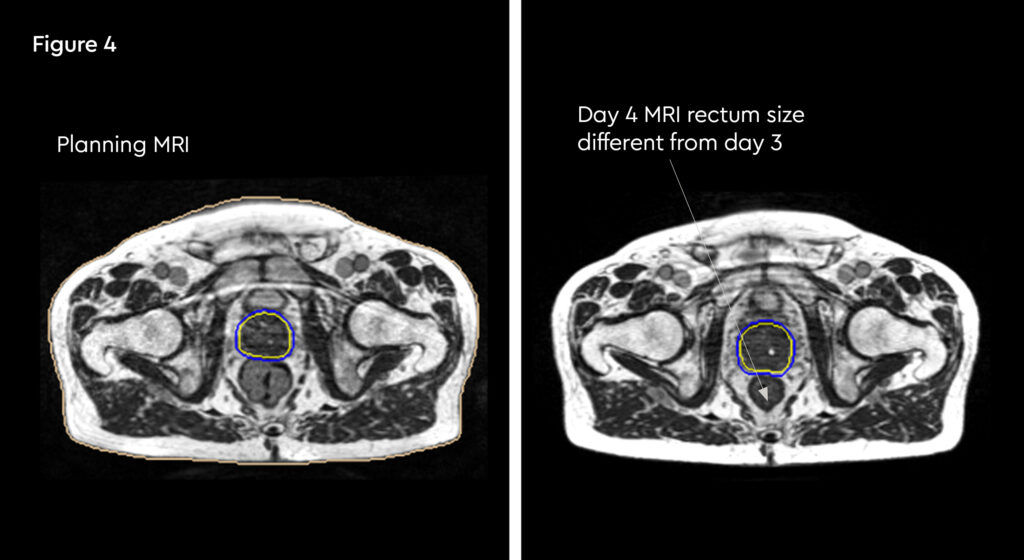

At each session, daily adaptation was performed to account for changes in the position of the prostate and for variable bladder and bowel filling. Figure 1 and figure 2 illustrate the typical differences seen between the original planning MRIdian scan and that seen on the day of treatment due to day-to-day organ movement. Figure 3 and figure 4 illustrate how these movements were accommodated with the on-table plan adaptation.

Fig 3: Prostate SABR delivery plan. Prostate volume covered by 95% isodose (green line, red arrow). Tight conformality at rectal/prostate boundary (white arrow), and rapid drop off of high dose (50% isodose, green line, green arrow) to optimise dose delivery to the prostate and limit dose to the rectum, reducing the risk of toxicity

Fig 4: Fraction 3, adapted plan, optimised for anatomy of the day. Prostate volume covered by 95% isodose (green line, red arrow). Tight conformality at rectal/prostate boundary (white arrow), and rapid drop off of high dose (50% isodose, green line, green arrow) to optimise dose delivery to the prostate and limit dose to the rectum, reducing the risk of toxicity

Fig 5: Radiotherapy plan

Fig 6: Plan adaptation. Tight conformality at rectal and prostate boundary is demonstrated by the arrow. Rapid reduction of high dose optimises dose delivery to the prostate and limit dose to the rectum, reducing the risk of long term toxicity.